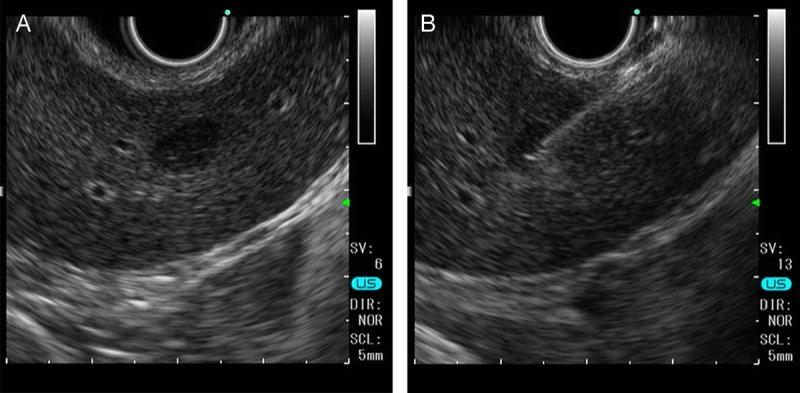

A suspected case of hepatic reactive lymphoid hyperplasia in which EUS-fine needle aspiration contributed to the diagnosis.

疑似肝反应性淋巴样增生病例,eus细针穿刺诊断。